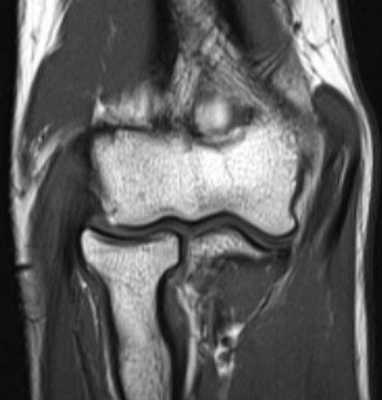

б)МРТ локтевого сустава в корональной плоскости. Общее сухожилие разгибателей в месте прикрепления к латеральному надмыщелку плечевой кости неравномерно утолщено, МР-сигнал от него неоднородно повышен на PD FS-ВИ и Т2-ВИ за счет выраженного отека и разволокнения (признаки латерального эпикондилита), общая целость его не нарушена. Окружающие мягкие ткани с признаками отека.